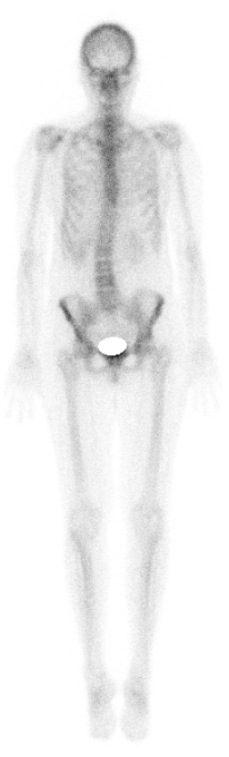

Nuklearmedizin

- Darstellung von Stoffwechselprozessen oder bestimmten Bindungsstellen im Körper.

- Funktion oder Funktionsstörung wird sichtbar.

- Häufig Nutzung bestimmter Stoffe, die der Körper ohnehin aufnimmt (z.B. Zucker). Daran Kopplung eines schwach radioaktiven Strahler (z. B. F-18), um den Weg im Körper zu verfolgen.

- Strahlung wird mit entsprechenden Geräten sichtbar gemacht (SPECT [SinglePhotonenEmissions ComputerTomograph] oder PET [PositronenEmissionsTomograph]).

- Nachteil: Strukturen können in ihrem Aussehen nicht bzw. schlecht erfasst werden.

Nuklearmediziner wissen also wie etwas funktioniert, aber nicht genau wie es aussieht.